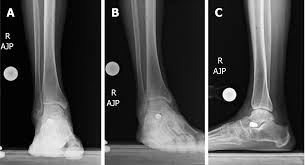

Force Needed To Unlock The Ankle Depending On Different Joint Positions Download Scientific Diagram

Force Needed To Unlock The Ankle Depending On Different Joint Positions Download Scientific Diagram from www.researchgate.net